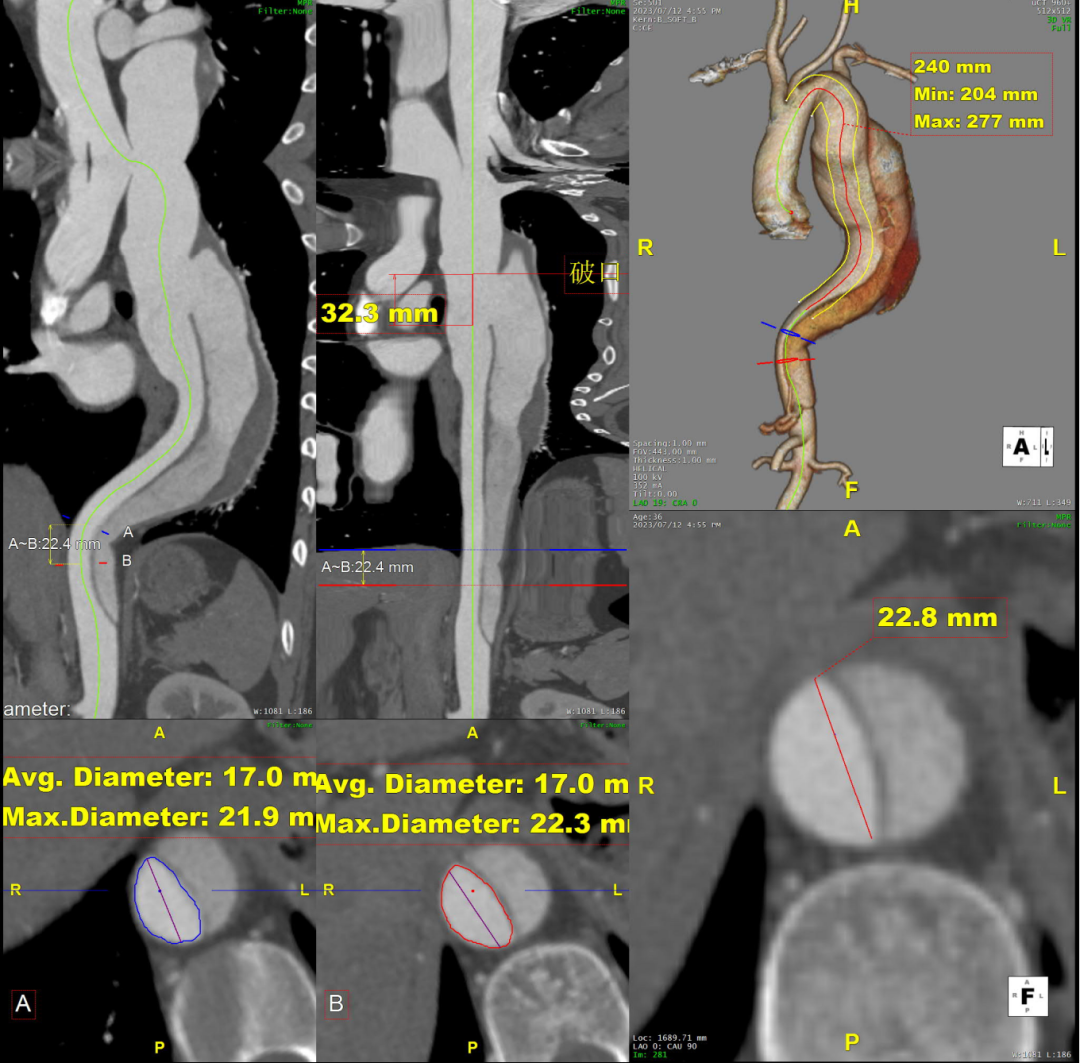

术前CTA评估与测量

术前CTA提示主动脉夹层(Stanford B型,Debake llI型),主动脉弓及降主动脉瘤样扩张,累及左锁骨下动脉起始段,管径最粗约7.4cm,夹层初破口位于降主动脉起始段,向下累及至腹主动脉(约平胸12椎体水平),真腔小,假腔大,腹腔干发自混合腔,肠系膜上动脉、下动脉,双肾动脉均起自真腔,双肾灌注未见差异。

术前三维重建

术前CTA详解:

病例特点

1. 弓型陡峭,成角;

2. 自左颈总后缘小弯侧锚定区不足1cm;

3. 巨大破口,约33mm,病变累及至腹腔干平面。